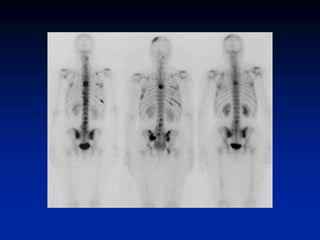

Superscan

• When the metastatic process is

diffuse, virtually all of the radiotracer

is concentrated in the skeleton, with

little or no activity in the soft tissues or

urinary tract. The resulting pattern,

which is characterized by excellent

bone detail, is frequently referred to as

a superscan

• A superscan may also be associated

with metabolic bone disease. Unlike in

metastatic disease, however, the

uptake in metabolic bone disease is

more uniform in appearance and

extends into the distal appendicular

skeleton.

Superscan • When themetastatic process is diffuse, virtually all of the radiotracer is concentrated in the skeleton, with little or no activity in the soft tissues or urinary tract. The resulting pattern, which is characterized by excellent bone detail, is frequently referred to as a superscan • A superscan may also be associated with metabolic bone disease. Unlike in metastatic disease, however, the uptake in metabolic bone disease is more uniform in appearance and extends into the distal appendicular skeleton.